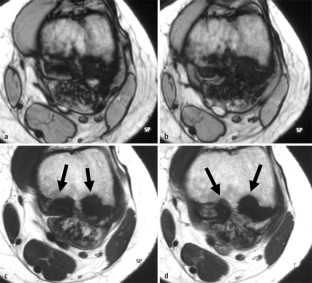

MRI morphology of bone tumors and tumor-like lesions

Für das Staging und die Charakterisierung von Knochentumoren und tumorähnlichen Läsionen ist in der Magnetresonanztomographie (MRT) der Einsatz von Spinechosequenzen erforderlich. Die MRT hat nur einen geringen Stellenwert in der Bestimmung der Dignität. Obwohl viele Knochentumoren und tumorähnliche Läsionen eine vergleichbare Morphologie in dieser bildgebenden Modalität aufweisen, können einige Tumorentitäten mittels MRT recht zuverlässig diagnostiziert werden. Hierzu zählen Knorpeltumoren, die solitäre und aneurysmatische Knochenzyste, der Riesenzelltumor, fetthaltige Läsionen und bis zu einem gewissen Grad auch das Osteoidosteom und das Osteoblastom. Es werden praktische Tipps gegeben, wann bei Tumorverdacht die MRT eingesetzt werden sollte, wie bei einem zufällig bei einer MRT gefundenen Tumor die Untersuchung modifiziert werden sollte und welcher Tumor vorliegen könnte.

Spin-echo sequences are mandatory at MRI for staging and characterization of bone tumors and tumor-like lesions. MRI is of minor value in the estimation of the malignant potential of an osseous lesion. Although many bone tumors and tumor-like lesions present similar morphology at MRI, some entities can be diagnosed with good reliability. These include chondrogenic tumors, solitary and aneurysmal bone cysts, giant cell tumors, lesions containing fatty tissue and, to a certain extent, osteoid-osteomas and osteoblastomas. Practical advice is given regarding when to perform a MRI study in cases of tumor suspicion. Further advices are given for cases a tumor is found incidentally at a MRI study, how to modify the study and which kind of tumor may be present.